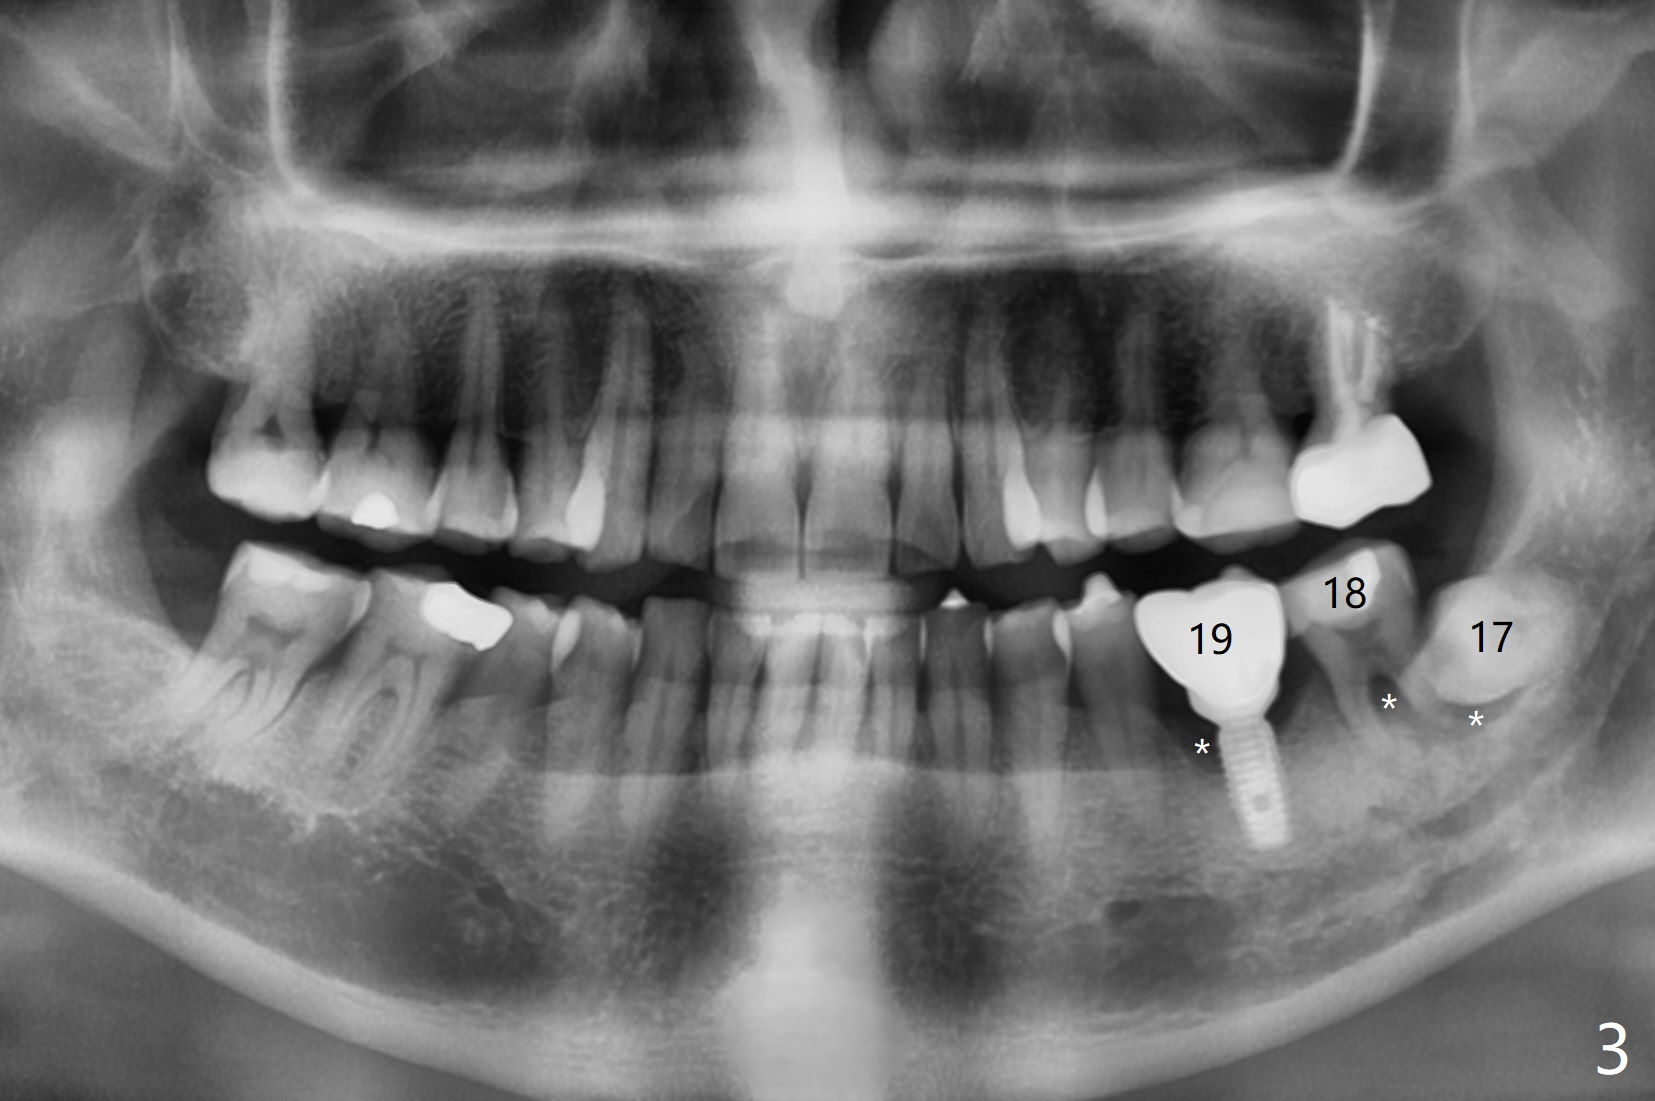

A 58-year-old man appears to have furca lesion or fracture the roots of the tooth #18 three years 5 months post cementation of #19 (Fig.1). In fact the abutment screw gets loose twice even with a buried screw driver. The implant at #18 will be a large tissue-level one (Fig.2). Use a thumb driver to place the implant initially through the metal sleeve for orientation. Although bone resorption mesial to #19 implant looks more severe in panoramic X-ray (Fig.3 *) and the sagittal view of CT (Fig.5) than PA (Fig.1), there is bone (less density) buccal (B) and lingual (Fig.5 *). Bone graft will be conducted at #19 if clinical exam confirms deep pocket the same time of #18 surgery. Distal radiolucency of #18 (Fig.3 *) makes it necessary to extract #17 simultaneously as well. Prepare Titanium brush.